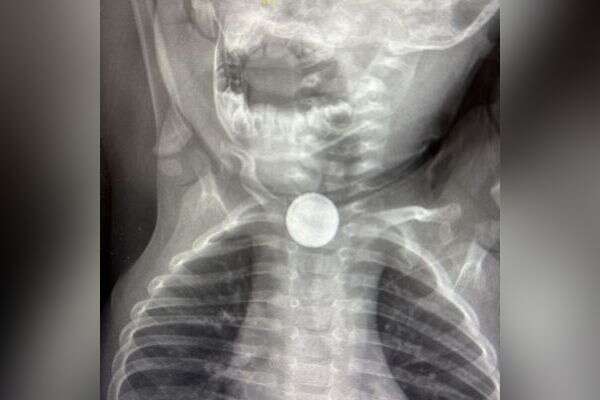

התינוק, שמתגורר באחד הכפרים בגליל, הובא עם הוריו למיון ילדים, בשעת לילה מאוחרת, לאחר שסבל מקשיים בבליעה, הזלת ריר והקאות. משיחה שנערכה עם הורי התינוק, עלה חשד שבלע סוללה של שעון ישן. בעקבות זאת הוכנס התינוק לניתוח חירום, במהלכו הוכנס אל תוך הוושט - בפעולה הנקראת "אסו-פגוסקופיה" - מכשיר דק דמוי צינור, כדי לאתר את הגוף הזר.

"אם הסוללה לא נשלפת תוך שעות ספורות, עלול להיגרם נזק בלתי הפיך, עד כדי סכנת חיים", הבהירו הרופאים, ונתנו טיפ שניתן לעשות במקרה של בליעת סוללה - לתת לפעוט כמה כפות דבש.

ד"ר מעיין גרובר, מנהל יחידת אף-אוזן-גרון ילדים הסביר כי בליעת סוללה היא דבר מסוכן במיוחד לתינוקות ולפעוטות, ואם אינה נשלפת מהגוף תוך שעות ספורות - עלול להיגרם נזק בלתי הפיך, ואף מצב של סכנת חיים. "מגע בין הסוללה והרוק גורם לתהליכי קורוזיה וכוויה כימית. הדבר עלול להוביל לכוויות חמורות, קרע בוושט, דימום, זיהום ופגיעה בכלי דם סמוכים. בנוסף, סוללה התקועה בוושט עלולה לחסום את צינור העיכול ולפגוע בנשימה ובבליעה".